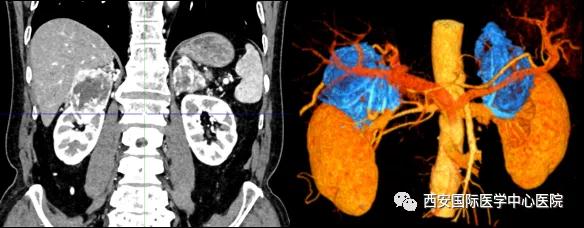

今年七十五歲的患者,來自陜西省商洛市,四月前因腰背部疼痛就診于當(dāng)?shù)蒯t(yī)院,行CT檢查發(fā)現(xiàn)“右腎、雙側(cè)腎上腺占位,前縱膈淋巴結(jié)腫大,雙肺多發(fā)結(jié)節(jié)、胸椎骨質(zhì)破壞,考慮轉(zhuǎn)移瘤”。為進(jìn)一步診斷治療,患者的兒子帶他來到西安某三甲醫(yī)院,查泌尿系CT提示“右腎占位性病變,多考慮腎癌,雙側(cè)腎上腺多發(fā)轉(zhuǎn)移灶,腹膜后多發(fā)腫大淋巴結(jié)”;行穿刺活檢提示“腎透明細(xì)胞癌”;并給予患者口服靶向藥物的治療方案。

自四月份至今,患者一直口服靶向藥物治療(阿昔替尼5mg 2次/日),期間無不良反應(yīng),目前腰背部疼痛癥狀也有所緩解,復(fù)查影像學(xué)資料提示瘤體較前縮小,腫瘤完整切除的可能性明顯提高;而且患者的兒子也是一名外科醫(yī)生,所以他更想為父親完成后續(xù)的手術(shù)治療。

患者一家慕名前來到西安國際醫(yī)學(xué)中心醫(yī)院找到楊增悅教授。楊增悅教授仔細(xì)看完患者的之前的影像學(xué)及病理資料后,診斷為:右腎透明細(xì)胞癌(T4N1M1);并安排他住院。而后,主管醫(yī)生及時(shí)為他完善了術(shù)前檢查及評估。7月15日,在麻醉手術(shù)中心柴偉主任、王彬榮副主任、李娟護(hù)士長、李瑞剛護(hù)士長及全體麻醉手術(shù)中心團(tuán)隊(duì)的有力保障下,成功完成了這臺“大”手術(shù)。

手術(shù)由楊增悅教授主持,舒濤主治醫(yī)師、王東主治醫(yī)師主刀,黃怡醫(yī)師、王平醫(yī)師協(xié)助完成。由于第四代達(dá)芬奇機(jī)器人更加靈活和精準(zhǔn)的特性,手術(shù)全程順利,尤其是完全精準(zhǔn)的“解鎖”了右腎動脈和右腎靜脈的數(shù)十根交互纏繞的分支血管。術(shù)后患者麻醉恢復(fù)后生命體征平穩(wěn),順利返回泌尿外科普通病區(qū)進(jìn)一步康復(fù)。